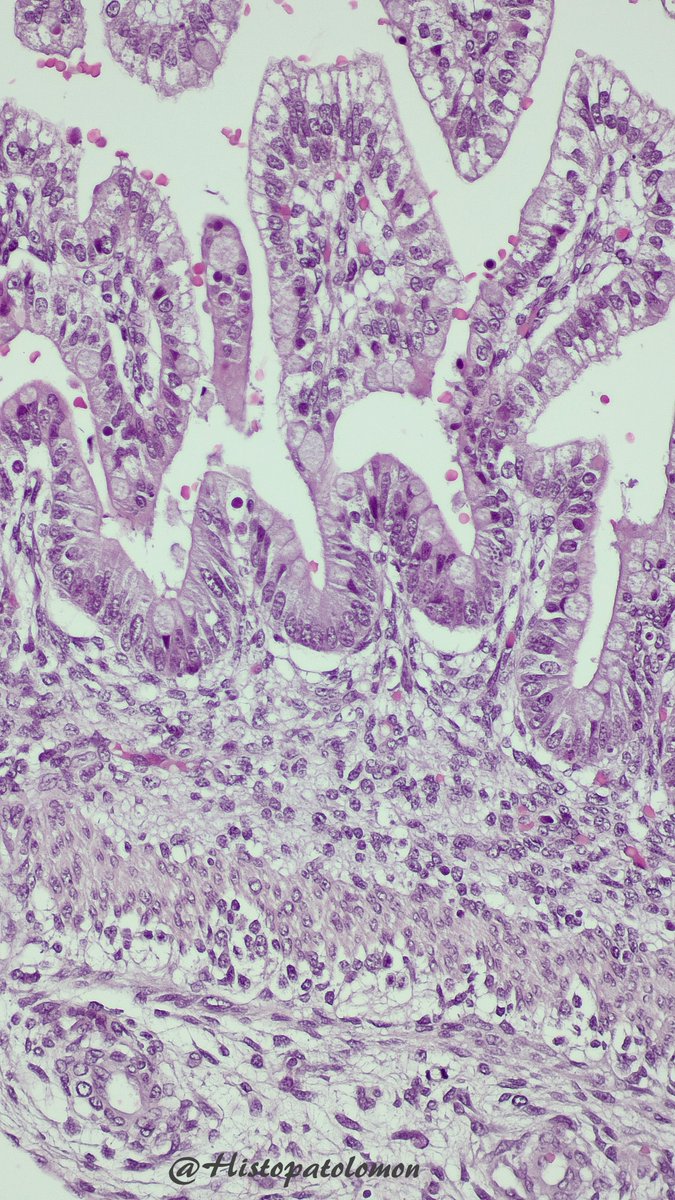

Isolated lymphoid follicles appear at 15-21 weeks and Peyer's patches at 25-29 weeks. As you can see, there is no muscularis mucosae (week 20) but there are goblet cells (week 7)